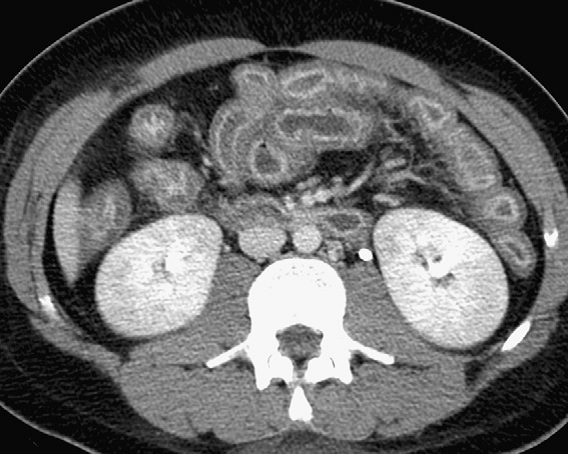

In older cystic fibrosis patients

“distal intestinal obstruction syndrome”

“meconium ileus” equivalent